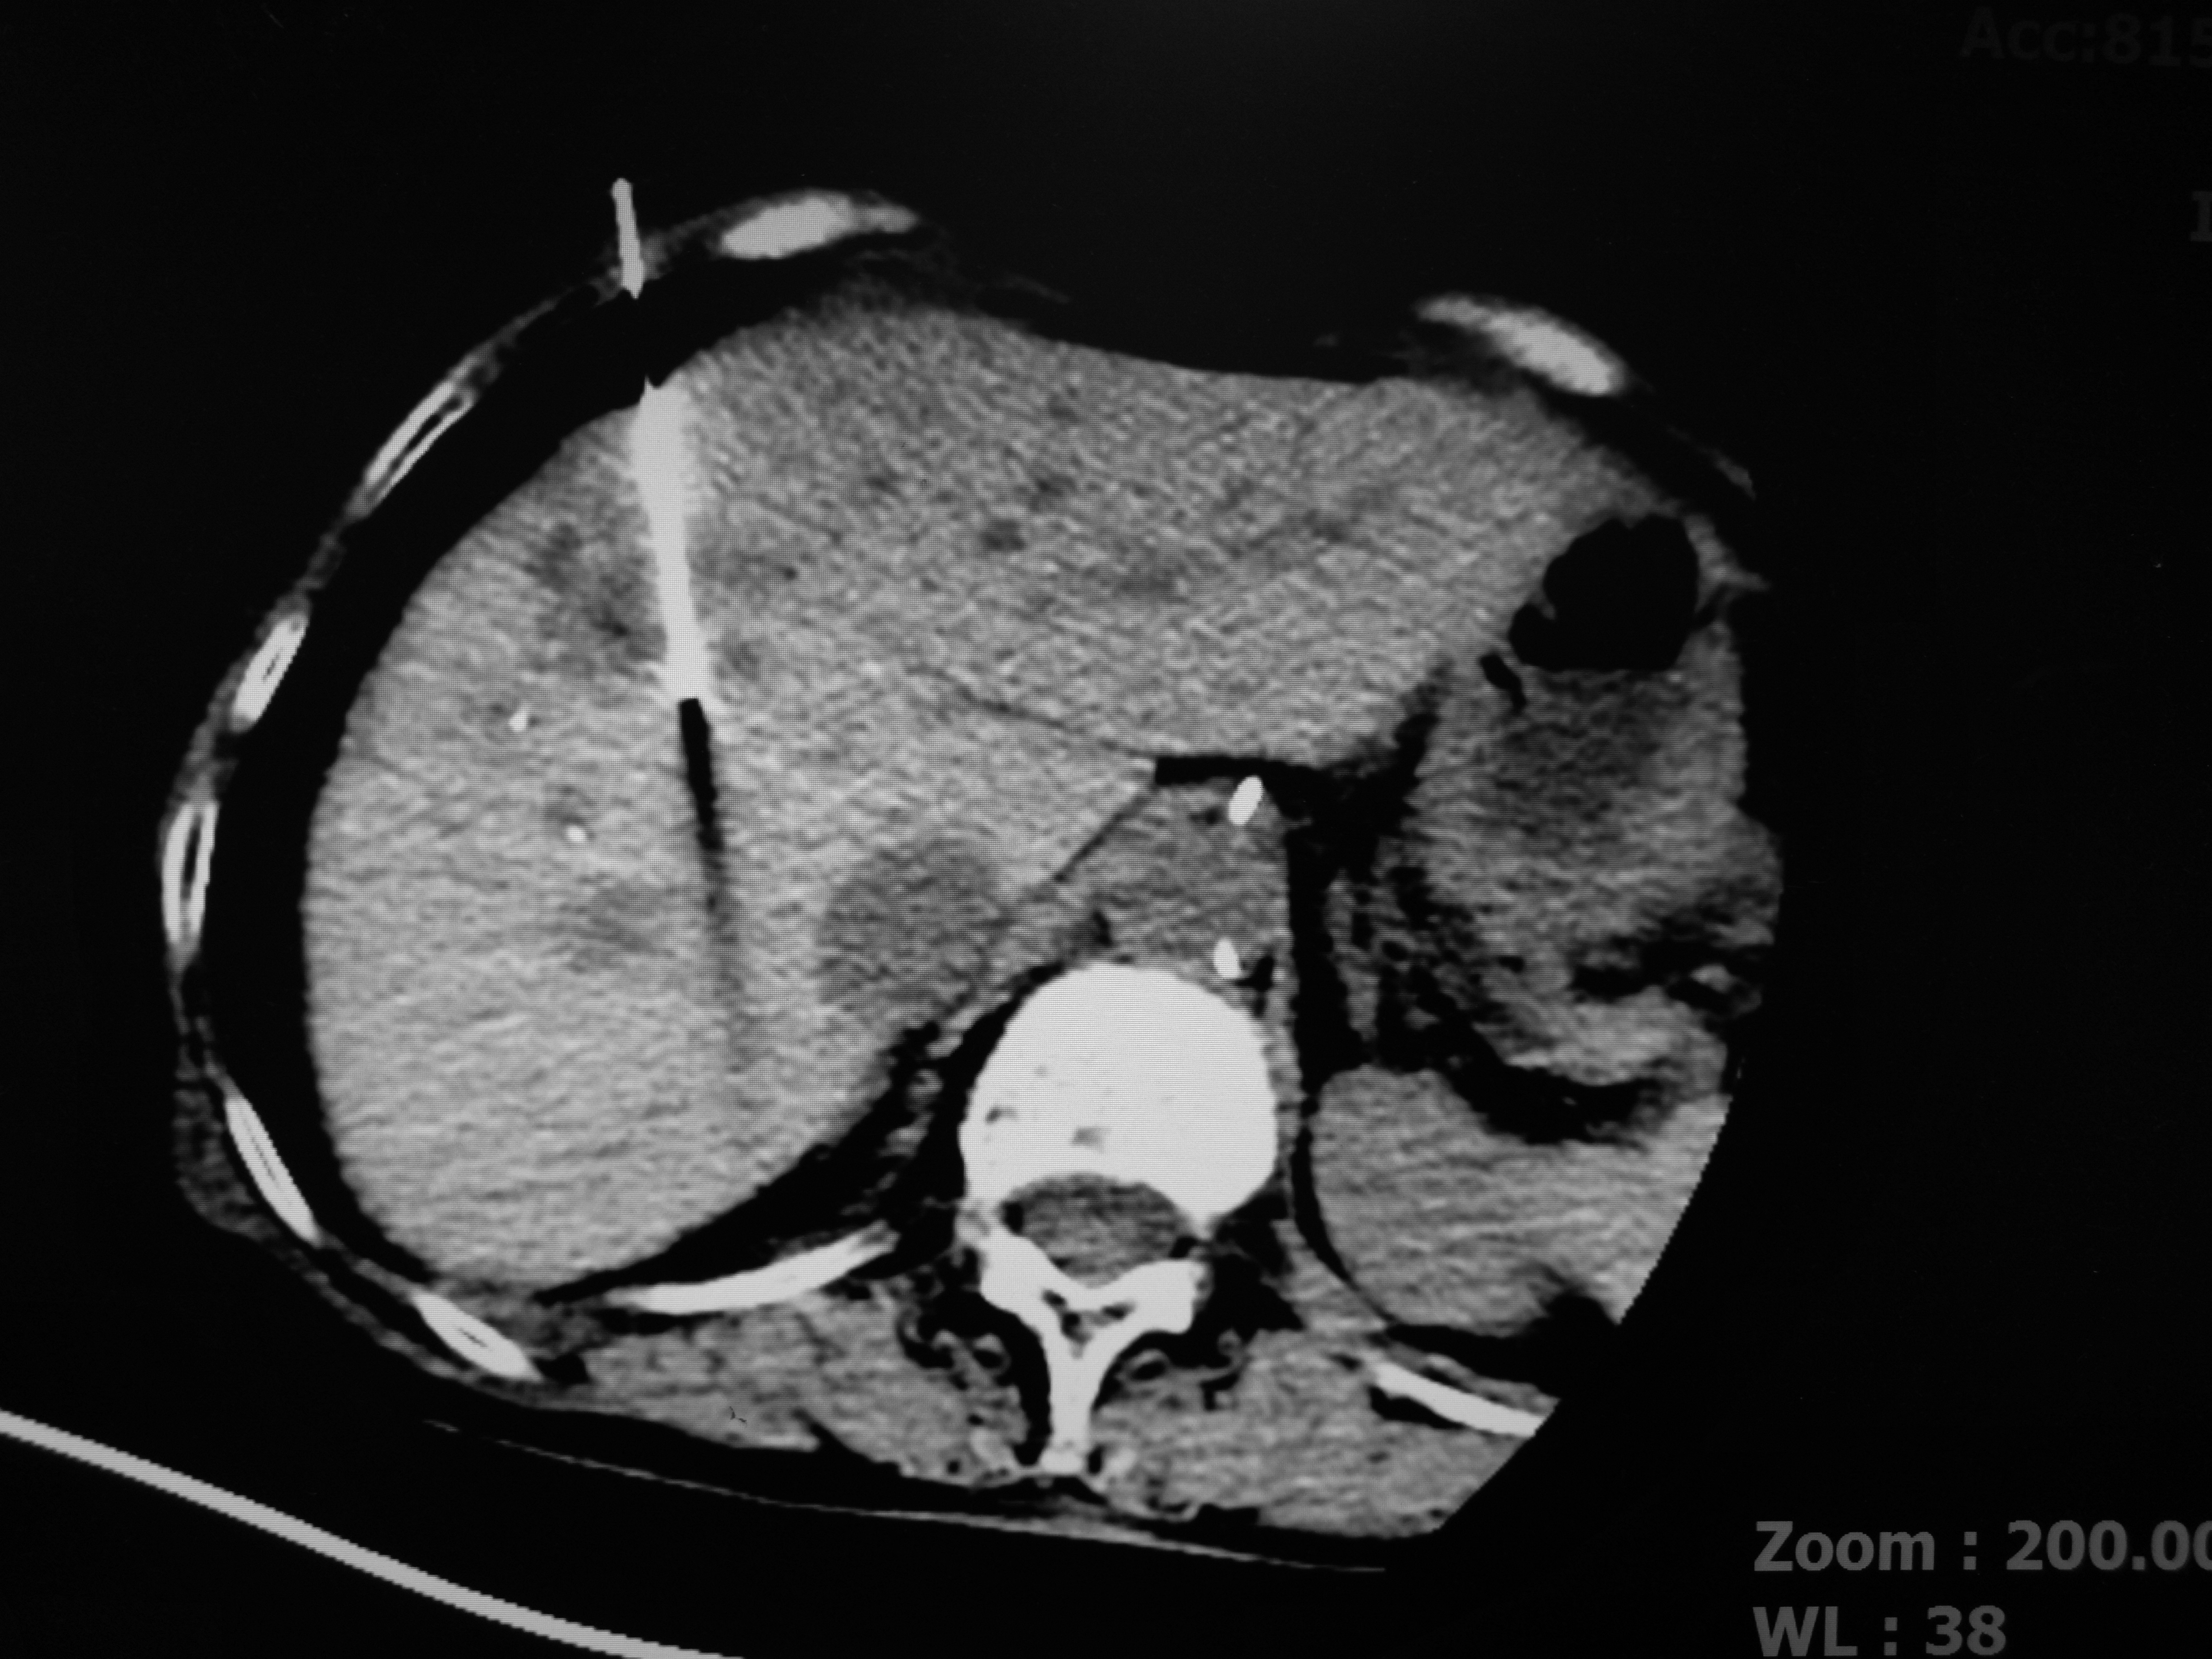

第三步:CT定位后,消融针穿刺到肿瘤

第四步:消融针插入肿瘤后,开机消融